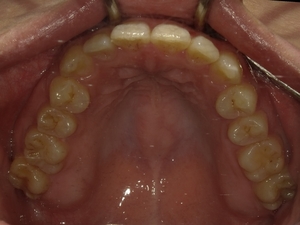

◯ご相談内容:歯並びが気になる◯矯正の種類:マウスピース型矯正「インビザラインGO」◯治療期間:20週間◯治療費用:44万円(税込)